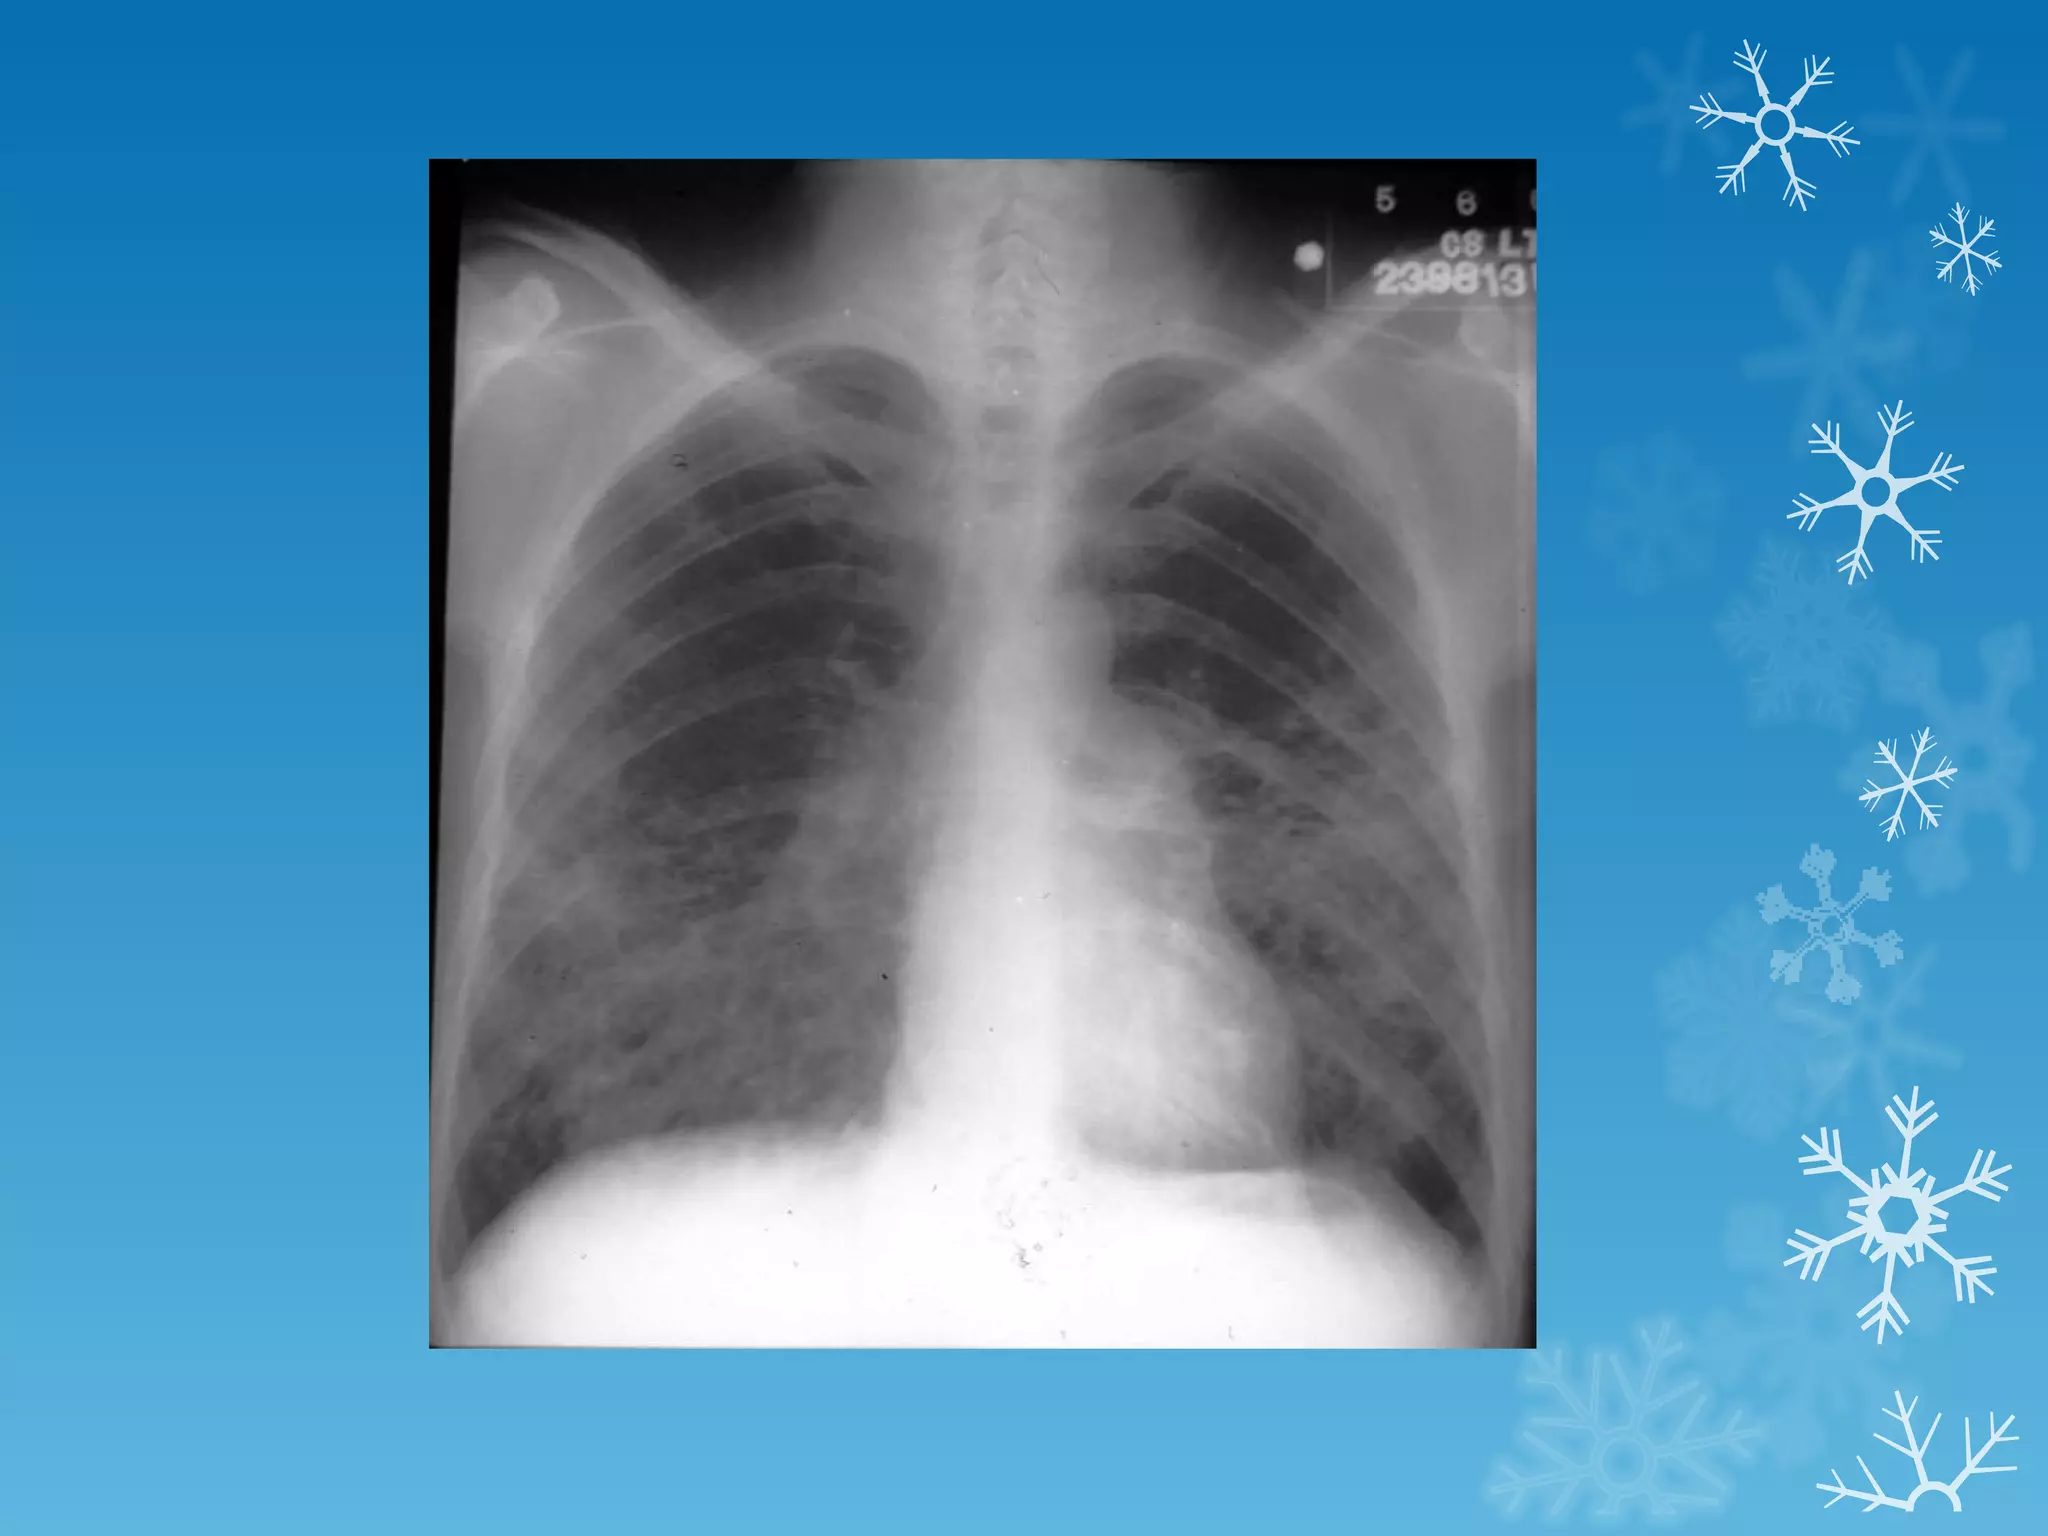

This document discusses chest x-ray interpretation and provides guidance on evaluating x-rays. It explains that tissue density determines how an x-ray beam penetrates, with denser tissues appearing whiter and less dense tissues appearing blacker. It also outlines different chest x-ray views and factors to consider like patient orientation, age, gender, and rotation. Abnormalities are described as appearing too white, too black, too large, or in the wrong place. The document stresses a systematic approach of identifying, localizing, describing lesions, and providing differential diagnoses.